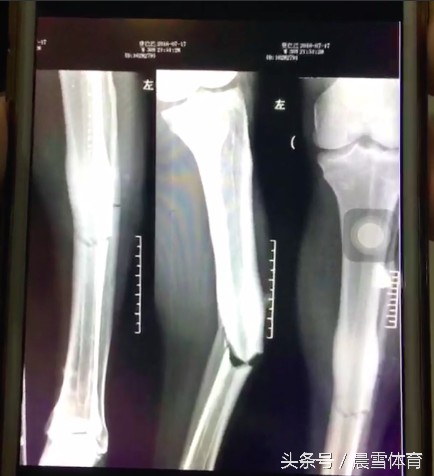

乌兰 在大连大学附属中山医院进行了3个半小时的手术,从X光片来看,乌兰的腓骨明显断裂,他需要3个月的康复时间才能下地走路,1年之后才能拆掉钢板,对他的职业生涯也造成了极大的影响。